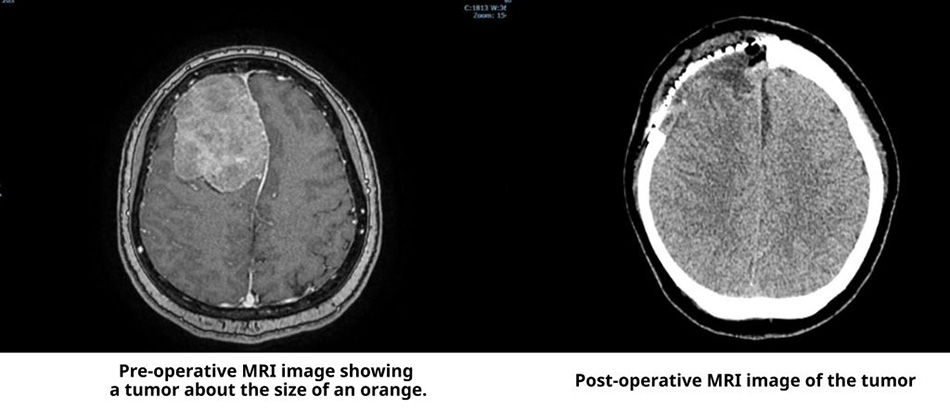

Ms Trinh Nhat Khanh, a 45-year-old martial arts instructor living in Ho Chi Minh City, occasionally experienced mild headaches and decided to undergo a stroke screening at FV Hospital. An MRI scan unexpectedly revealed a large meningioma measuring over 6 cm in diameter — approximately the size of an orange — compressing nearly a quarter of her brain.

MRI reveals orange-sized tumour in patient’s brain.

“The tumour had developed over a long period, allowing the skull to adapt to it, which made it difficult to detect. Although the patient experienced only occasional headaches and her higher brain functions remained unaffected, surgery was urgently needed. If the tumour grew any larger, it could trigger serious complications such as seizures or even become life-threatening,” explained Dr Tran Luong Anh, Specialist Level II and Head of Neurosurgery and Spine Surgery at FV Hospital.